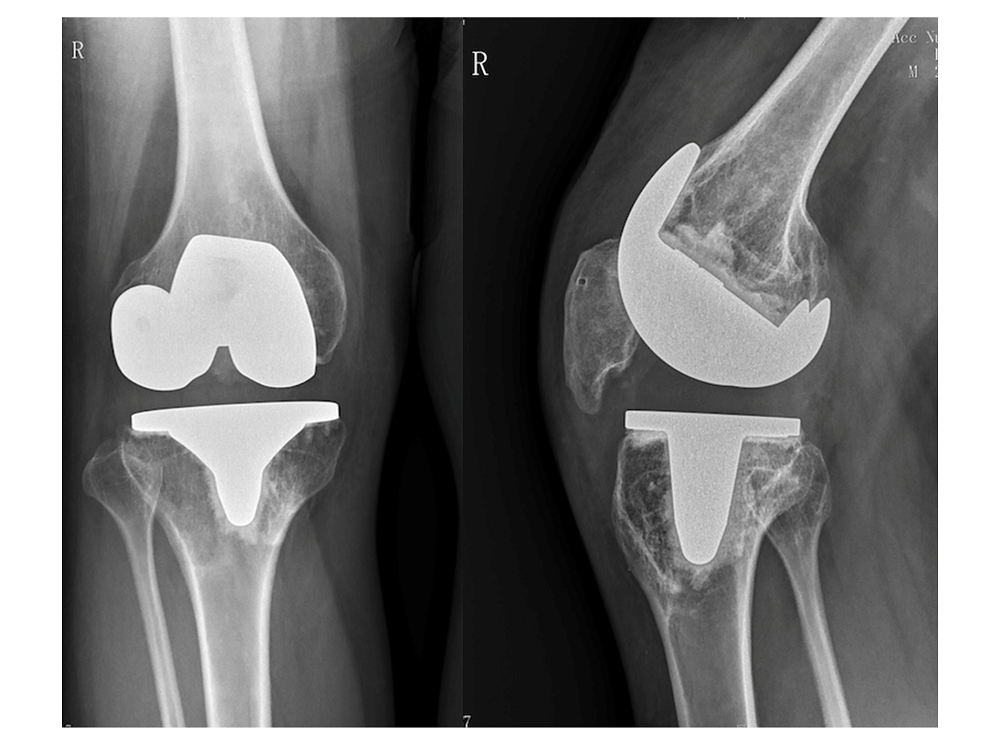

术后X线 右膝关节置换 假体位置良好